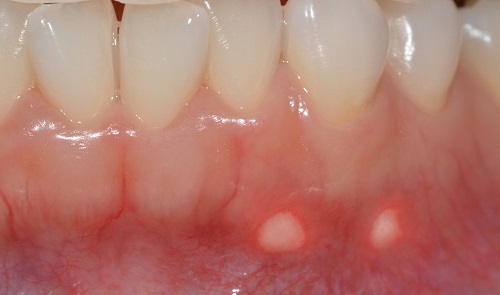

구내염의 가지 수에는 첫 번째로 궤양의 종류인 아프타성 궤양이 있어요. 뺨과 혀, 입술 안쪽에서 생기는 붉은 고리 속 옅은 노란색 궤양의 형태를 보입니다.

재발성 질병인 아프타성 궤양의 원인은 유전성, 많은 면역반응, 염증성 사이토카인의 증가와 관련이 있을 것으로 가설하고 있습니다.

구강 내 자극으로 인한 스크래치가 생겼거나 많은 스트레스와 피로를 최고 많은 사유로 짐작하였으있다고 합니다. 복취하는 식단(커피, 초콜릿, 치즈, 감귤류, 견과류, 감자..)이나 약물, 임신 중 그렇지 아니하면 피임약 복용 중에 발생하기도 하며 금연을 할 때에 나타나는 기회가 잦다고 하고요.

또 비타민B, 철분, 엽산이 부족할 때에도 일으켜서 난다고 합니다.